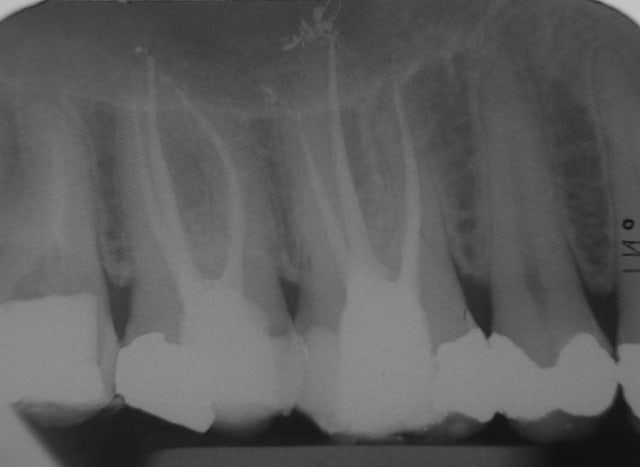

obturations au thermafil de 16 et 17. Les jolies petits puffs ont été faits avec le AH Plus jet (AH plus en seringue, très pratique pour placer dans le canal, mais il faut utiliser une pointe de papier pour l'étaler). Eviter d'en mettre trop.